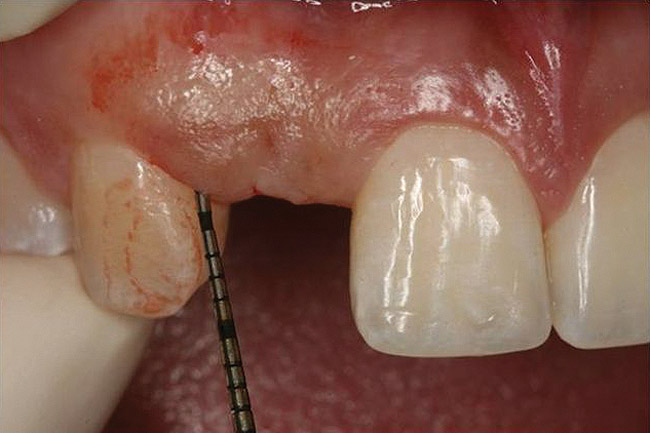

Figure 10  Clinical examination of the bound edentulous space: Measurement of the distal (Fig 10) and mesial (Fig 11) interproximal tissue height using a periodontal probe supplements data obtained from the periapical radiograph. Estimation of the buccal tissue thickness (bone sounding) is performed at the determined location of the gingival zenith using a guide developed from the diagnostic waxing (Fig 12).

Figure 11   Clinical examination of the bound edentulous space: Measurement of the distal (Fig 10) and mesial (Fig 11) interproximal tissue height using a periodontal probe supplements data obtained from the periapical radiograph. Estimation of the buccal tissue thickness (bone sounding) is performed at the determined location of the gingival zenith using a guide developed from the diagnostic waxing (Fig 12).

Figure 12   Clinical examination of the bound edentulous space: Measurement of the distal (Fig 10) and mesial (Fig 11) interproximal tissue height using a periodontal probe supplements data obtained from the periapical radiograph. Estimation of the buccal tissue thickness (bone sounding) is performed at the determined location of the gingival zenith using a guide developed from the diagnostic waxing (Fig 12).